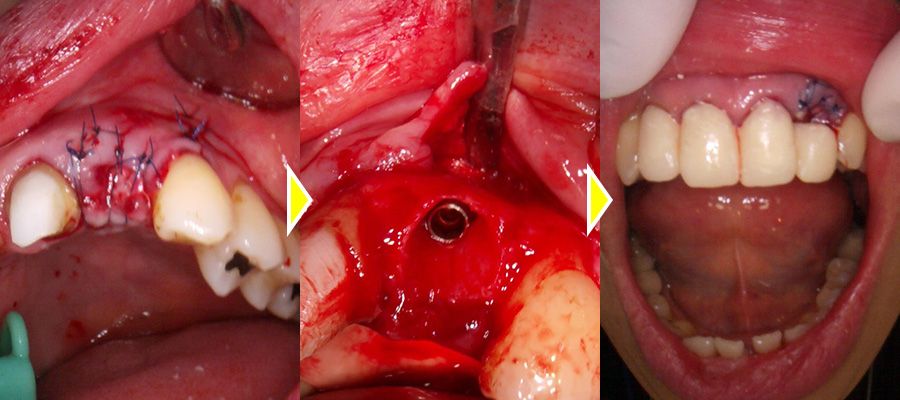

前歯のクラウン除去、中の土台の型取り、仮歯の作成をまず行い、次に左上2番の抜歯、インプラントの埋入、骨造成仮歯へまでを1回のオペで行いました。

抜歯窩を確認すると、膿が大きく唇側に穴が開いていることが確認できます。

骨欠損の範囲が大きかったため骨造成も同時に行いました。

骨造成の際には骨補填材が穴からはみ出てしまわないよう歯肉を剥離し、唇側からも合わせて骨造成を行いました。

術後は定期的にチェックを行い、5ヶ月起き、インプラント体と骨が結合していることが確認できてから上部、他の前歯部の印象も行いました。

次に被せ物ができてからインプラント上部とクラウンのセットを同日に行いました。

術後は見た目も綺麗になりか大変満足していただいています。